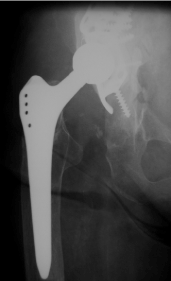

Clinical examination revealed limping due to insufficiency of the pelvtrochanteric muscles. ROM was fine with extension / flexion 0/0/100°, abduction/adduction 20/0/20°, external rotation/ internal rotation 30/0/30°. Scar was normal. X ray of the right hip showed a stable stem with no signs of loosening, destruction of the greater trochanter and reconstruction of the acetabulum (Figure 1).

Figure 1. X-ray of the right hip (ap view): Total hip arthroplasty with a stable stem with no signs of loosening, destruction of the greater trochanter and reconstruction of the acetabulum using an acetabular reinforcement ring.